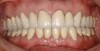

If the centric relation and centric occlusion in the presence of tooth surface loss is the same, or the dento-alveolar compensation has occurred, the teeth should be restored.54 The restorations can include Class V or palatal restorations, or reproduction of the cusps (Figure 9). Also, restorations can include covering the affected tooth surfaces with resin-based composites, using a sandwich technique, or placement of metallic, porcelain-fused-to-metal, or ceramic crowns (Figure 10, Figure 11, Figure 12, Figure 13, Figure 14, Figure 15 and Figure 16).

Figure  14  Full-mouth rehabilitation with porcelain-fused-to-metal.

Figure 14